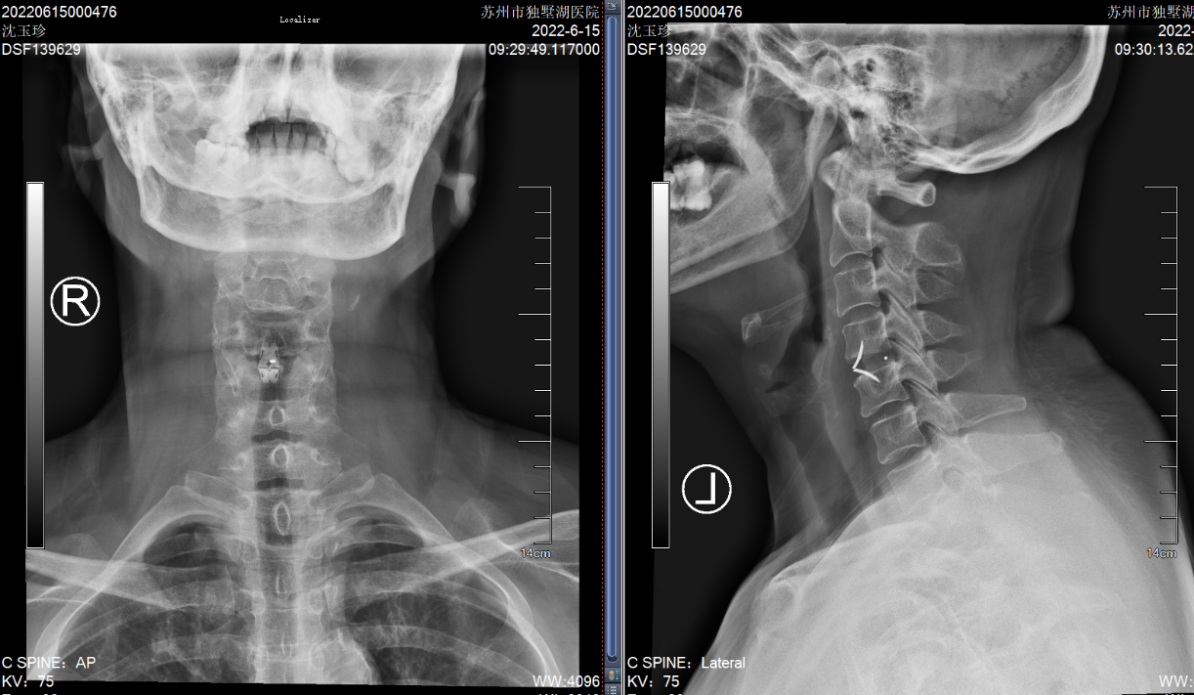

就在吕飞出院的当天,另一位症状相似的脊髓型颈椎病患者吕艳也来办理了住院手续。原来她是吕飞的亲姐姐,今年46岁。姐弟俩的症状和影像学表现都几乎相同,可见颈椎后纵韧带骨化确有一定的家族遗传倾向。吕艳告诉我们,他们姐弟这些年看过不少医生,都建议尽早手术,但因为听说颈椎手术风险极高,所以一直都选择“拖字诀”处理。这次吕飞的手术效果,给了她极大的信心和勇气,她毫不犹豫地也选择来做手术。

(姐姐的颈椎CT显示她的颈椎椎体同样存在明显的后纵韧带骨化,与弟弟不同的是,她的韧带骨化程度更严重)

(吕姐的接受的手术与吕弟一样,C3~6椎管扩大成形术。)